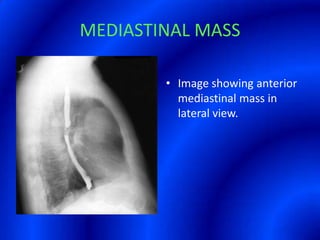

This document provides information about a barium swallow procedure. It begins with an introduction and overview of the embryology and anatomy of the pharynx and esophagus. It then describes the procedure itself, including preparation, technique, views obtained, and indications. Specific conditions that may be examined include pharyngeal and esophageal webs, foreign body impaction, scleroderma, dysphagia, mediastinal masses, and carcinoma. Diagrams are provided to illustrate normal anatomy and various pathological findings.